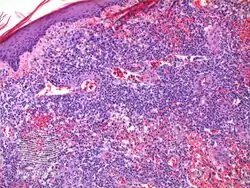

It has been described as "clinically benign but histologically malignant."[6]

Diagnosis of lymphomatoid papulosis is done via the presentation and a skin biopsy[7]

Lymphomatoid papulosis/pathology -

Lymphomatoid papulosis/pathology